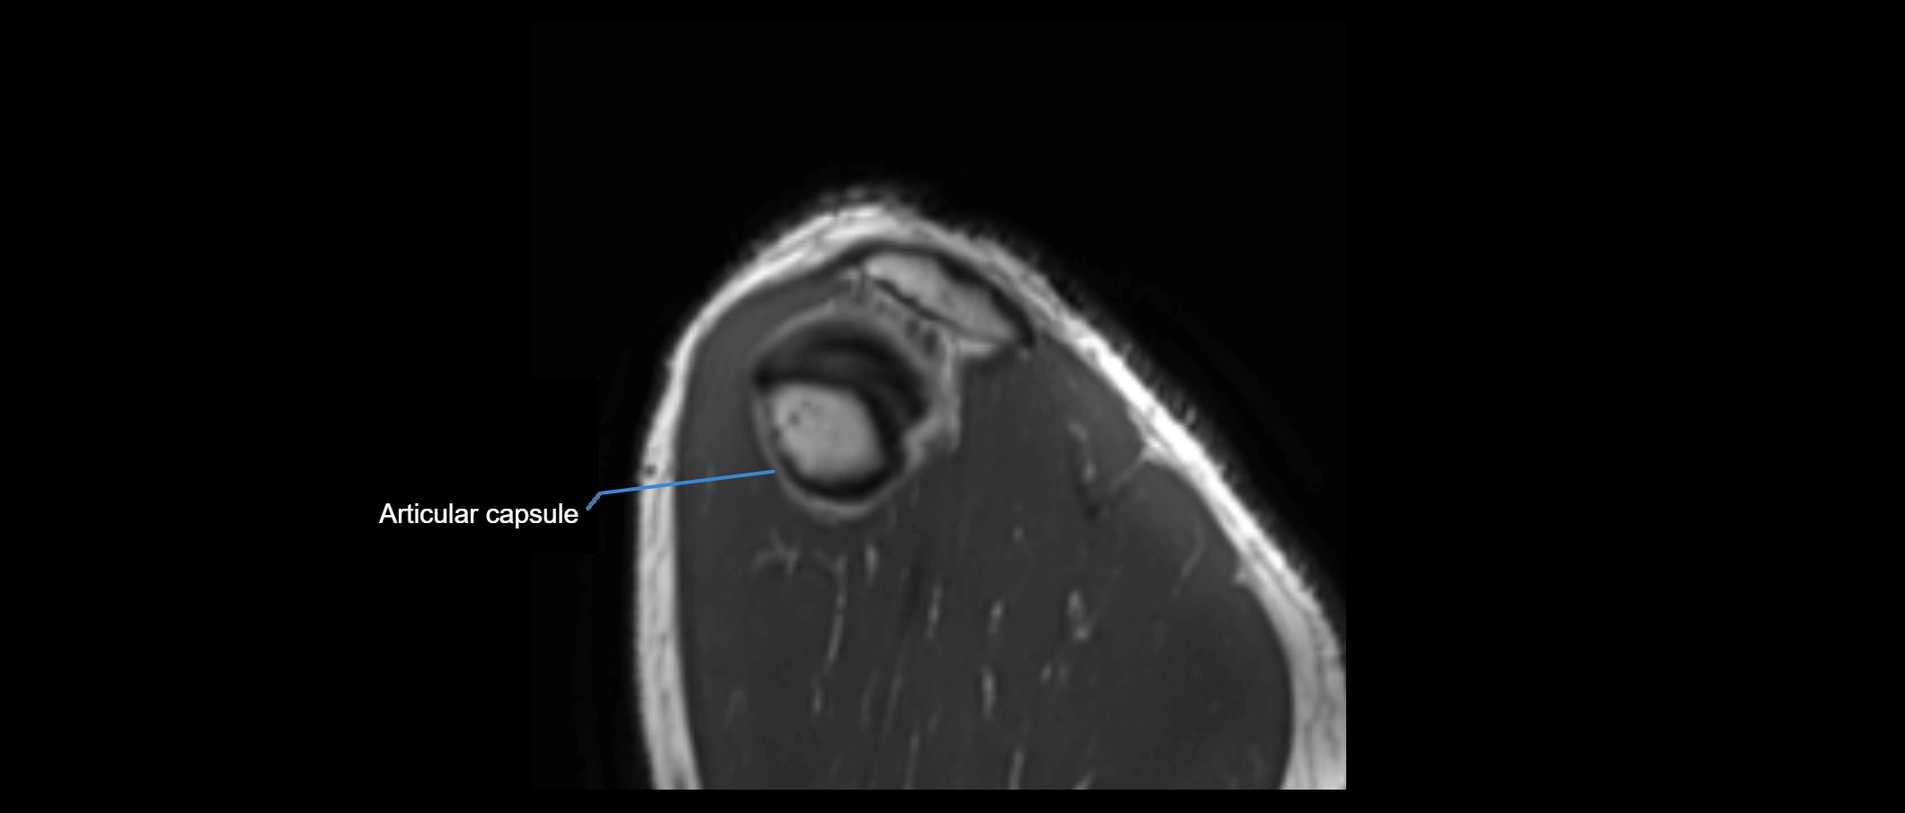

MRI images

image